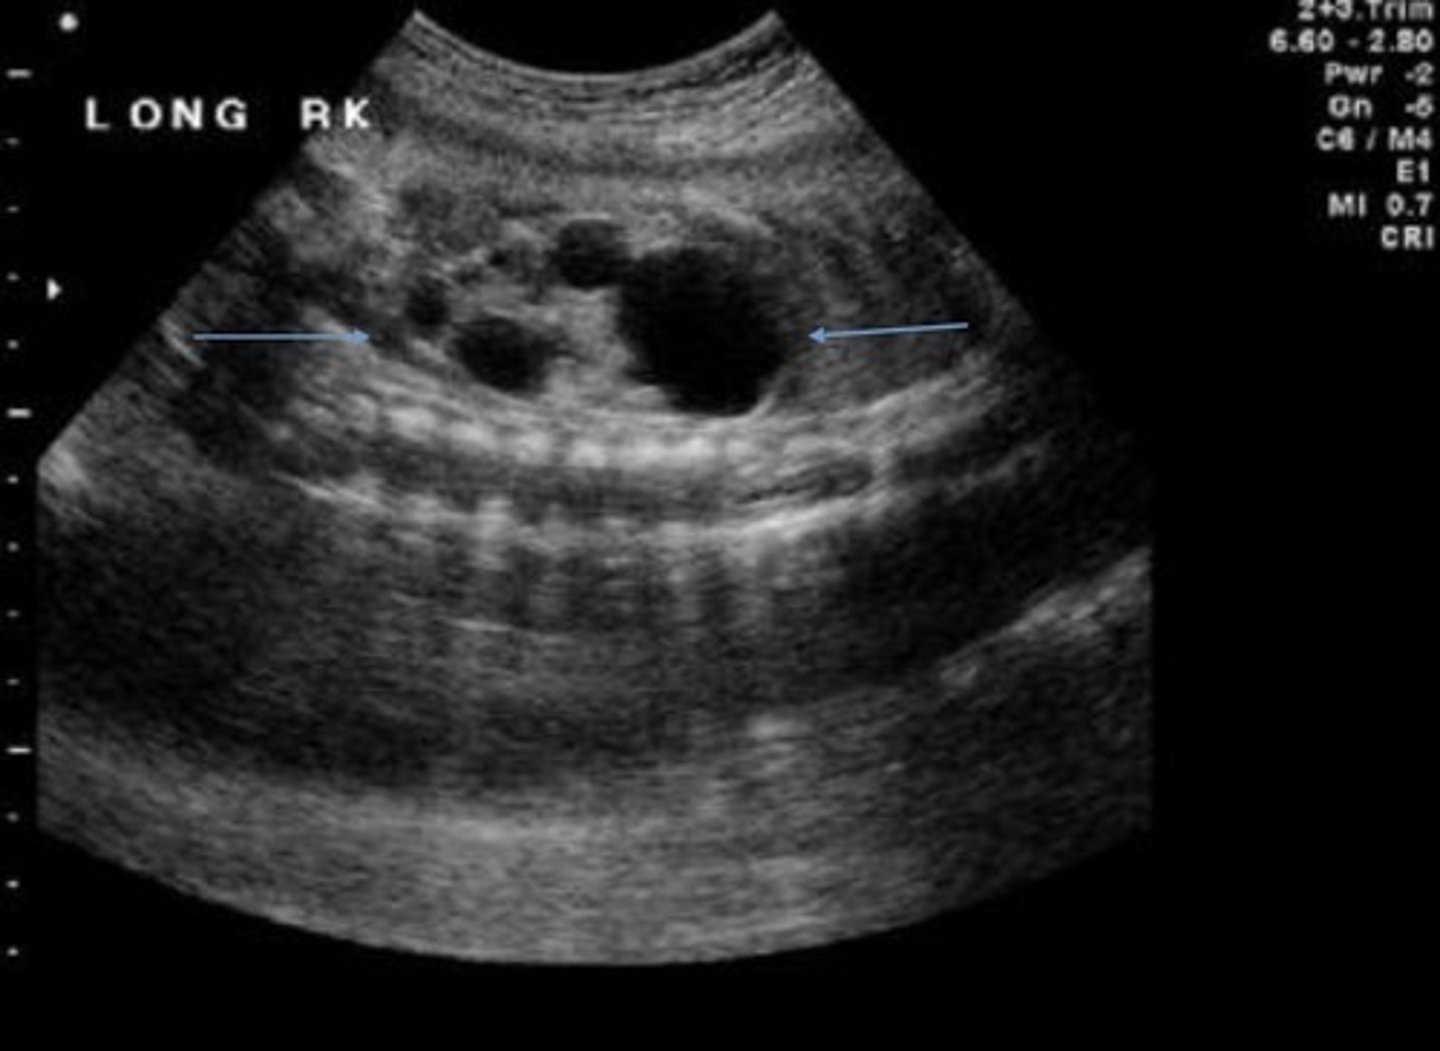

Grade 3 Hydronephrosis

Pelvis is > 10 mm

Marked dilation of calyces

Cortex is normal